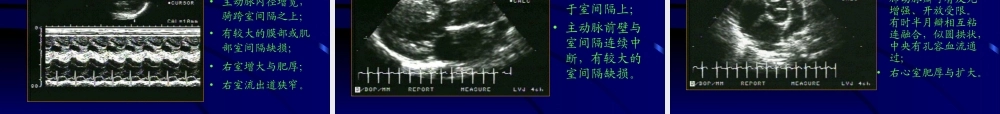

•二尖瓣曲线回声增粗,反光增强;•EF斜率减慢,A峰逐渐消失,为城垛样曲线;•舒张朗二尖瓣后叶运动与前叶同向;•左房、右室增大。一、二尖瓣狭窄第十章心脏瓣膜病是风湿性心瓣病中最常见的病变之一,其超声心动图有较大的特征性。•二尖瓣叶回声增粗,增强;•瓣尖粘连辩体活动尚可时,舒张期前叶瓣体膨向左室流出道,呈圆顶状凸起,失去正常的柔软度及二次开放运动;•后叶随前叶同向运动,还可有腱索增粗、缩短等改变。一、二尖瓣狭窄第十章心脏瓣膜病•左室短轴清楚显示二尖瓣开放面积缩小;•左房、右室增大,左心耳内可有附壁血栓的异常回声团。一、二尖瓣狭窄第十章心脏瓣膜病一、二尖瓣狭窄第十章心脏瓣膜病显示经二尖瓣舒张期湍流频谱,峰值流速增快,可闻声信号带尖啸声。一、二尖瓣狭窄第十章心脏瓣膜病彩色血流显像示经二尖瓣口多色镶嵌型彩色湍流.似喷泉样。•二尖瓣前叶CD段于收缩中晚期或全收缩期有吊床样下垂;•当合并二尖瓣关闭不全时有左室高流量改变:即二尖瓣前叶、室间隔与左室后壁搏幅增大,还可有左房、左室增大。第十章心脏瓣膜病二、二尖瓣脱垂伴二闭二尖瓣脱垂以往很难确诊,自从超声心动图发展以来,由于其特征性图像而使诊断趋于简便。•二尖瓣形态松软稍肥厚、增大、运动活跃;•二尖瓣前后叶收缩期接合异常,于收缩期瓣叶向左房脱出并超过瓣环联线;•合并二尖瓣关闭不全时,可有左房、室增大及左室高流量改变。第十章心脏瓣膜病二、二尖瓣脱垂伴二闭•对二尖瓣关闭不全时的诊断具有特异性。•在左房内可探及收缩期宽带湍流。第十章心脏瓣膜病二、二尖瓣脱垂伴二闭彩色血流显像示左房内收缩期以蓝色为主的多色镶嵌型彩色返流束。第十章心脏瓣膜病二、二尖瓣脱垂伴二闭•主动脉根部的主动脉瓣回声增粗,反光增强且可有多条回声及钙化块状回声;•正常的六边形开放盒变小,一般前后径小于15mm。第十章心脏瓣膜病三、主动脉瓣狭窄主动脉口狭窄分瓣膜型、瓣下型(即肥厚型梗阻性心肌病)与瓣上型,而以瓣膜型为最常见。超声心动图对鉴别不同部位狭窄有肯定价值。•空间隔与左室后壁对称性向心性肥厚;•二尖瓣前叶曲线的EF斜率减慢,A峰增高或出现突出的B点。第十章心脏瓣膜病三、主动脉瓣狭窄•主动脉瓣回声粗,反光强,开放幅度小,有时还有辩叶钙化;•升主动脉有狭窄后扩张现象;•于主动脉瓣短轴观有时可看到畸形的半月瓣如先天性二叶式主动脉瓣。第十章心脏瓣膜病三、主动脉瓣狭窄第十章心脏瓣膜病三、主动脉瓣...